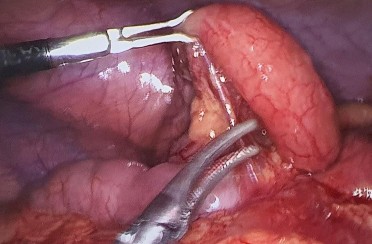

Hình 3.6: Hình ảnh thâm nhiễm mỡ xung quanh RT.

BN Dương Thị Kim A. 30 tuổi, mã bệnh án 2107075. Kết quả GPB viêm ruột thừa mủ. Phẫu thuật nội soi thấy ruột thừa viêm mủ sưng to, xung huyết, có thâm nhiễm mỡ.